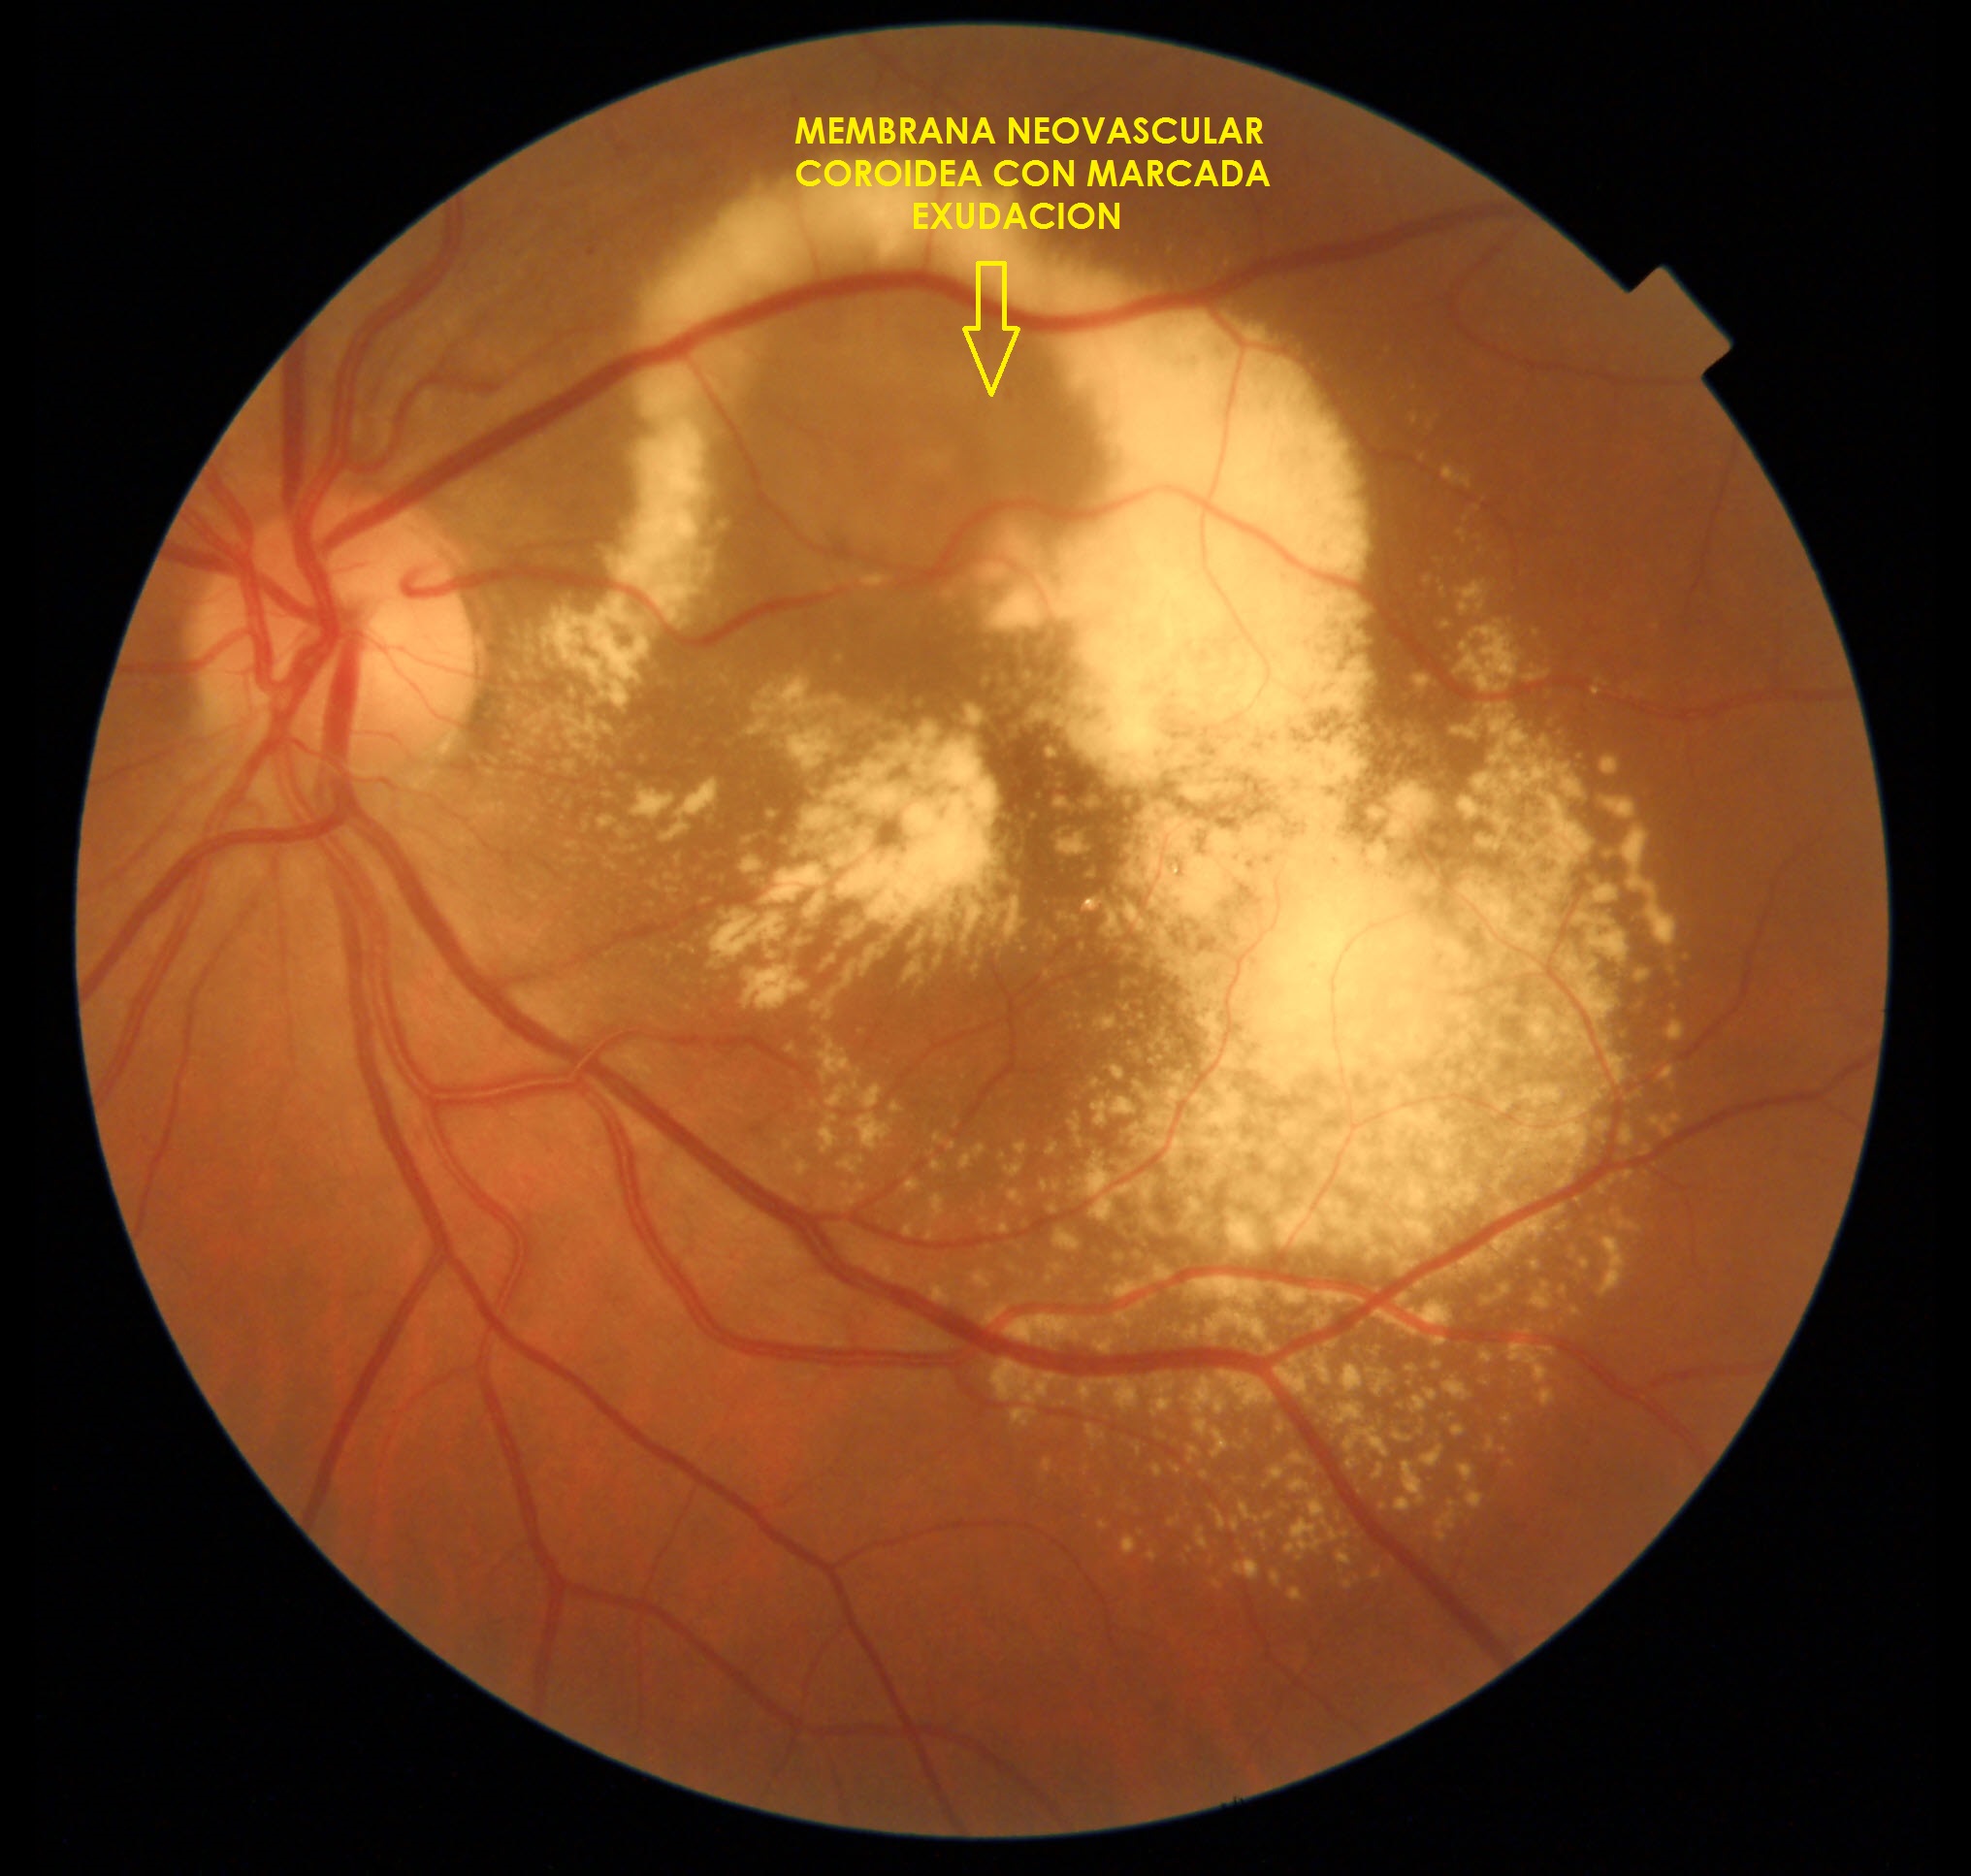

Degeneración Macular Relacionada con la Edad (DMRE)

Es una enfermedad que afecta principalmente a la macula, al presentarse afecta la visión central, la cual es necesaria para conducir automóviles, leer un libro o reconocer caras.

Tiene dos formas de presentación: Seca y Húmeda.

Forma Húmeda:

- Inyecciones intraoculares: La forma húmeda puede tratarse con medicamentos inyectados dentro del ojo (Anti VEGF).